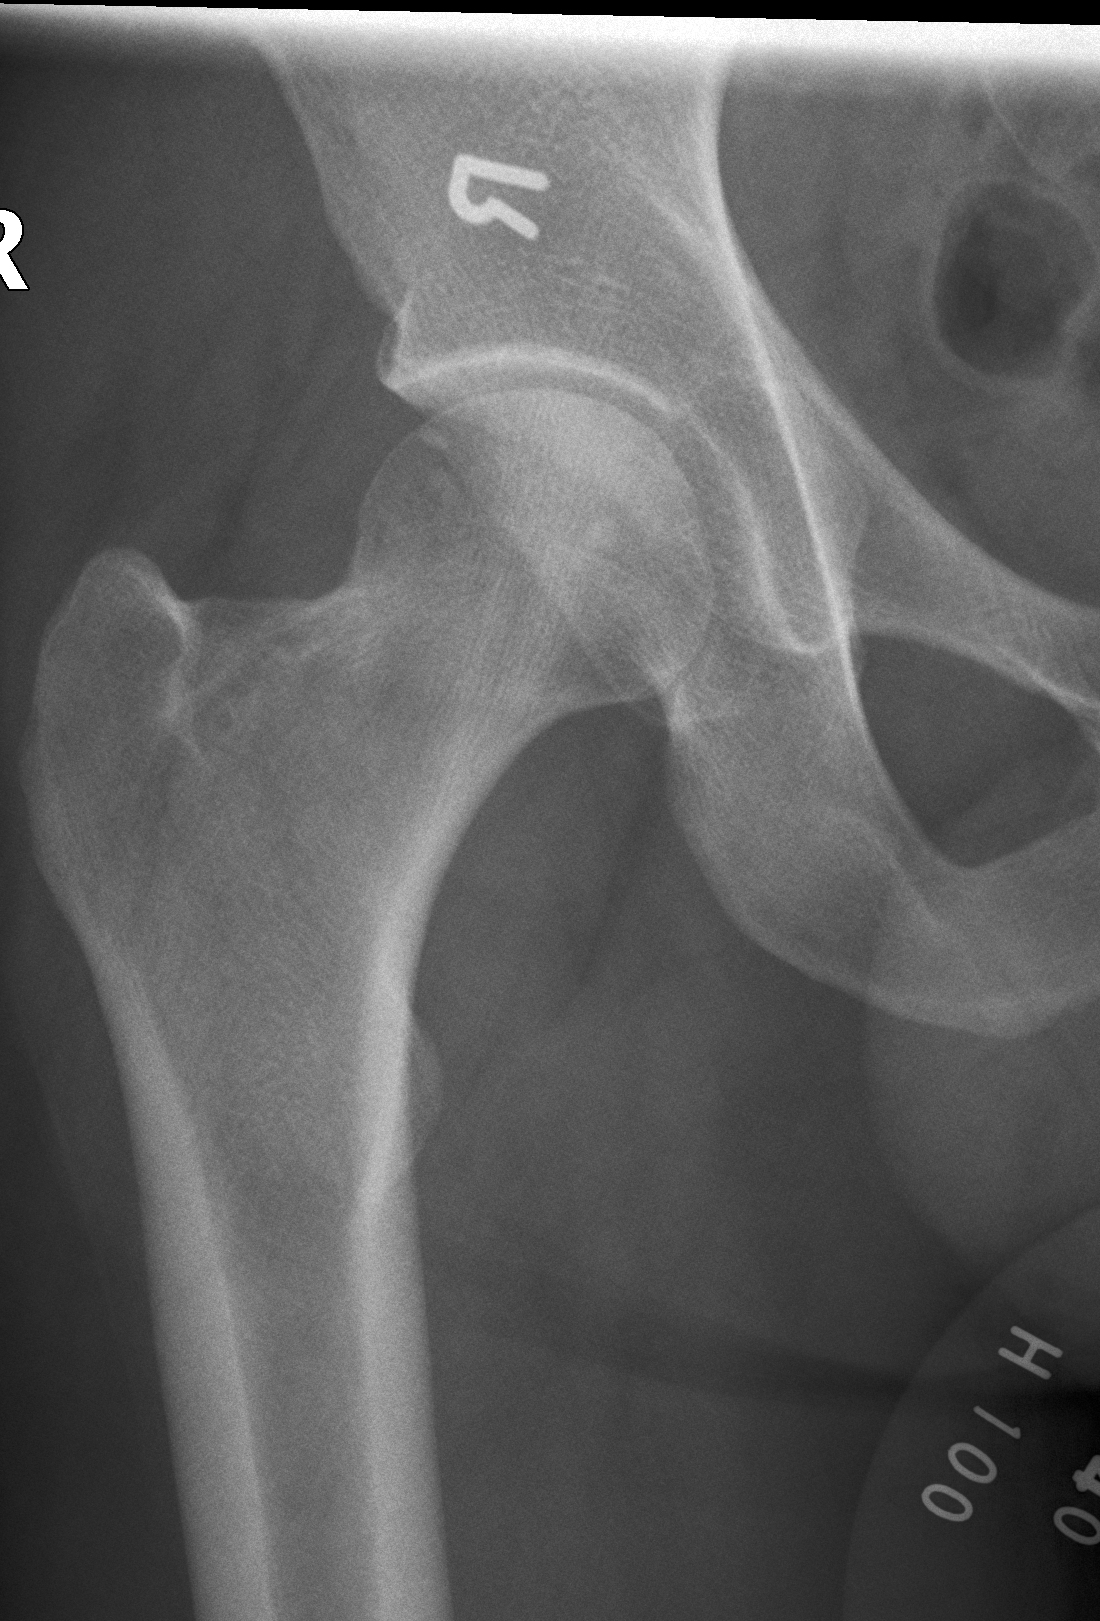

白色文字(排除指定关键词) Imaging Anatomy: interactive PACS-like atlas of radiological anatomy

解剖学模块